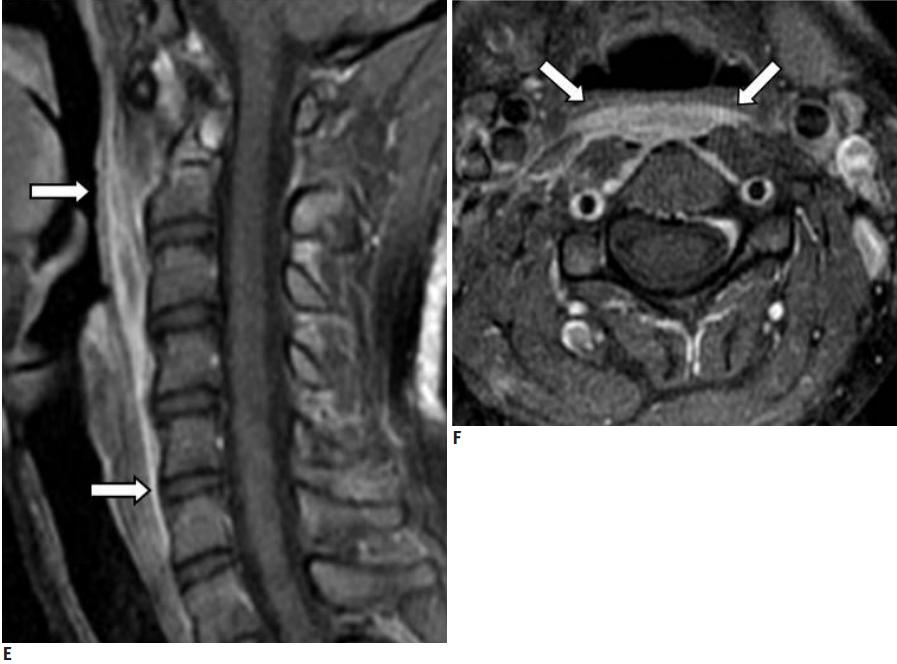

CT的高分辨率能够明确肌腱内的钙化,能够明确是钙化而不是其他骨骼来源的高密度影。 钙化一般位于寰椎前弓的下方和枢椎齿状突的前方,少部分可位于下颈椎前侧 。CT有助于明确椎体前积液的存在和排除其他病理表现,如骨折或脓肿。MRI对诊断不是必须,但有时可帮助确定软组织异常,排除咽后脓肿,脊椎炎或肿瘤。 MRI检查T2加权在椎前可见局限性的裂隙样区域,大多位于C1-4水平,呈高信号改变,这反应是由于炎症引起的积液 。T2加权、脂肪抑制序列和T1加权对鉴别积液和脂肪组织、含脂肪的骨髓以及咽后感染、脊椎炎有重要作用。MRI检查在钙化检查方面存在不足,T2加权呈低信号。

30岁女性,诊断为颈长肌钙化性肌腱炎,但钙化位于不寻常的位置:C4-5椎间隙前侧。A:颈椎侧位片示寰枢椎半脱位(长箭头)和椎前软组织肿胀(无线箭头);B,C和D:颈椎MRI示C1-6椎前软组织肿胀伴积液,D示齿状突骨侵蚀(无线箭头)

上述病人,E为增强,F为抑制像,G和H:经非甾体抗炎药治疗3天后查颈椎CT示C4-5椎前无定形钙化。

上述病人,I和J: 入院4天后复查颈椎MRI示椎前积液明显减少; K,随访2个月复查CT示C4-5前钙化灶减小。(PMID: 21852912)